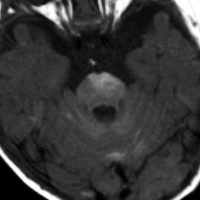

生下時に皮膚の大きな先天性色素細胞母斑があり脳MRIでみられたもの

有毛性母斑があるためにMRIが撮影されました。生後2ヶ月のものです。脳溝に沿うように,灰白質に浸潤するように,散在性の病変がみられます。脳幹部の前面から脳幹内部に浸潤するメラノーシスも特徴的です。